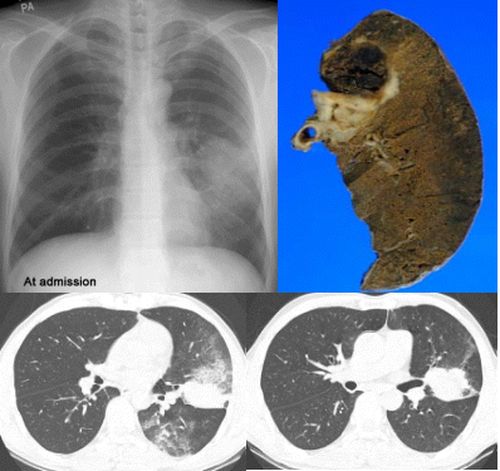

再来个空洞性肺癌,男,58岁,有咳嗽,咳痰,咯血,我看到片子时已经是治疗后复查了,第一次片子,空洞里充满了积液。

[本贴已被 jiajie 于 2006-3-8 19:19:06 修改过]